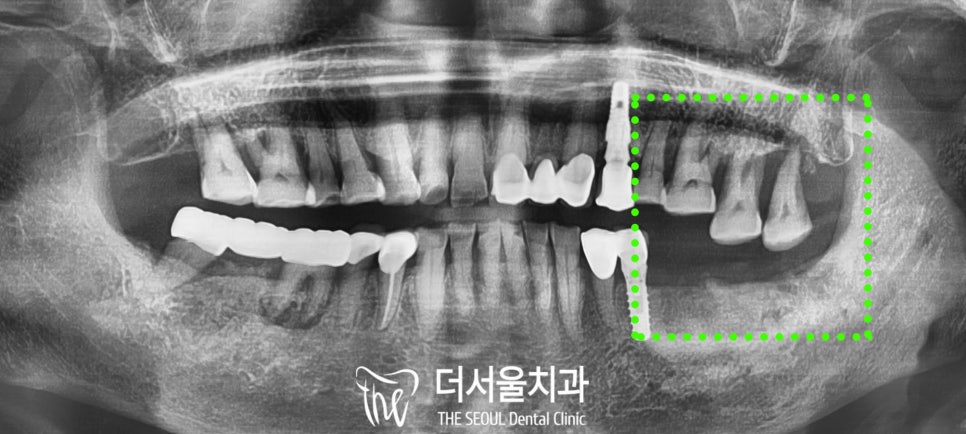

왼쪽 아랫니의 결손 부위로 인해

윗니에서 정출이 진행되었습니다.

정출치 발치 후 위아래 임플란트 식립

진단해 드렸습니다.

그리고 양쪽 어금니 모두 치주조직의

예후가 좋지 않아 보여

왼쪽 위아래 임플란트 먼저 진행한 후

왼 : 발치 후, 오 : 임플란트 식립 후

다시 돌아와서 현재 건강을

고려하여 위와 같이 발치하였고

위아래 무사히 임플란트 식립을 마쳤습니다.

위 사진은 오른쪽 치료를 위한

엑스레이인데요,

오른쪽 위아래 어금니 역시 잇몸뼈가 많이 낮아지고,

뿌리 끝 염증은 물론 치아의 동요도 있어

마찬가지로 발치를 진행했습니다.